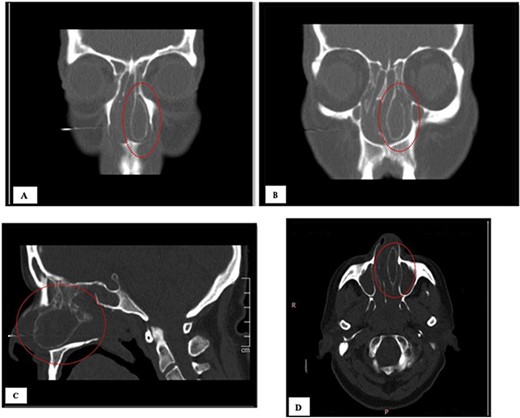

A 64-year-old female presented to our clinic complaining of nasal obstruction more to left side, postnasal discharge, and intermittent headache, anosmia, and facial discomfort since 1 year ago. She had sought previous medical advice and was on intranasal steroid spray and nasal saline irrigation without any improvement, her symptoms affecting the quality of life. She is not known history of allergy; she is not a smoker. She does not have any significant past medical or surgical history. On examination, anterior rhinoscopy showed: left nasal cavity huge mass reaching to left nostril and deviated nasal septum to the right. The endoscopic exam showed huge left-sided nasal mass reaching the level of left nostril, the scope cannot be passed to left-sided nasal cavity, right-sided endoscopic examination showed deviated nasal septum, discharge was appreciated from right middle meatus and along with edematous middle meatus. The nasopharyngeal examination showed post-nasal discharge over the wall without any mass. Rest of complete ears, throat, neck, and cranial nerves examinations were normal. The patient underwent head and paranasal sinus computed tomography (CT) scan, and it shows that this giant CB was pushing the septum to right, as well obstructing sinuses regular drainage contributing to the chronic sinusitis symptoms (Fig. 1). The patient was admitted to hospital for functional endoscopic sinus surgery, left CB release, excision, and septoplasty (Fig. 2). The specimen was collected in a formalin and send to further evaluation and came confirming the diagnosis with “polypoid fragment of respiratory mucosa with cystic space and inflammation,” and it was negative for any malignancy. No perioperative or postoperative complications were seen. The post-operative period showed excellent improvement in patient symptoms. Her quality of life much improved, she is on regular follow up in the clinic along regular nasal endoscopic examination with no evidence of disease recurrence till 12 months post-surgical intervention.

(A, B) CT of coronal view; (C) CT of sagittal view, and (D) CT of axial view.